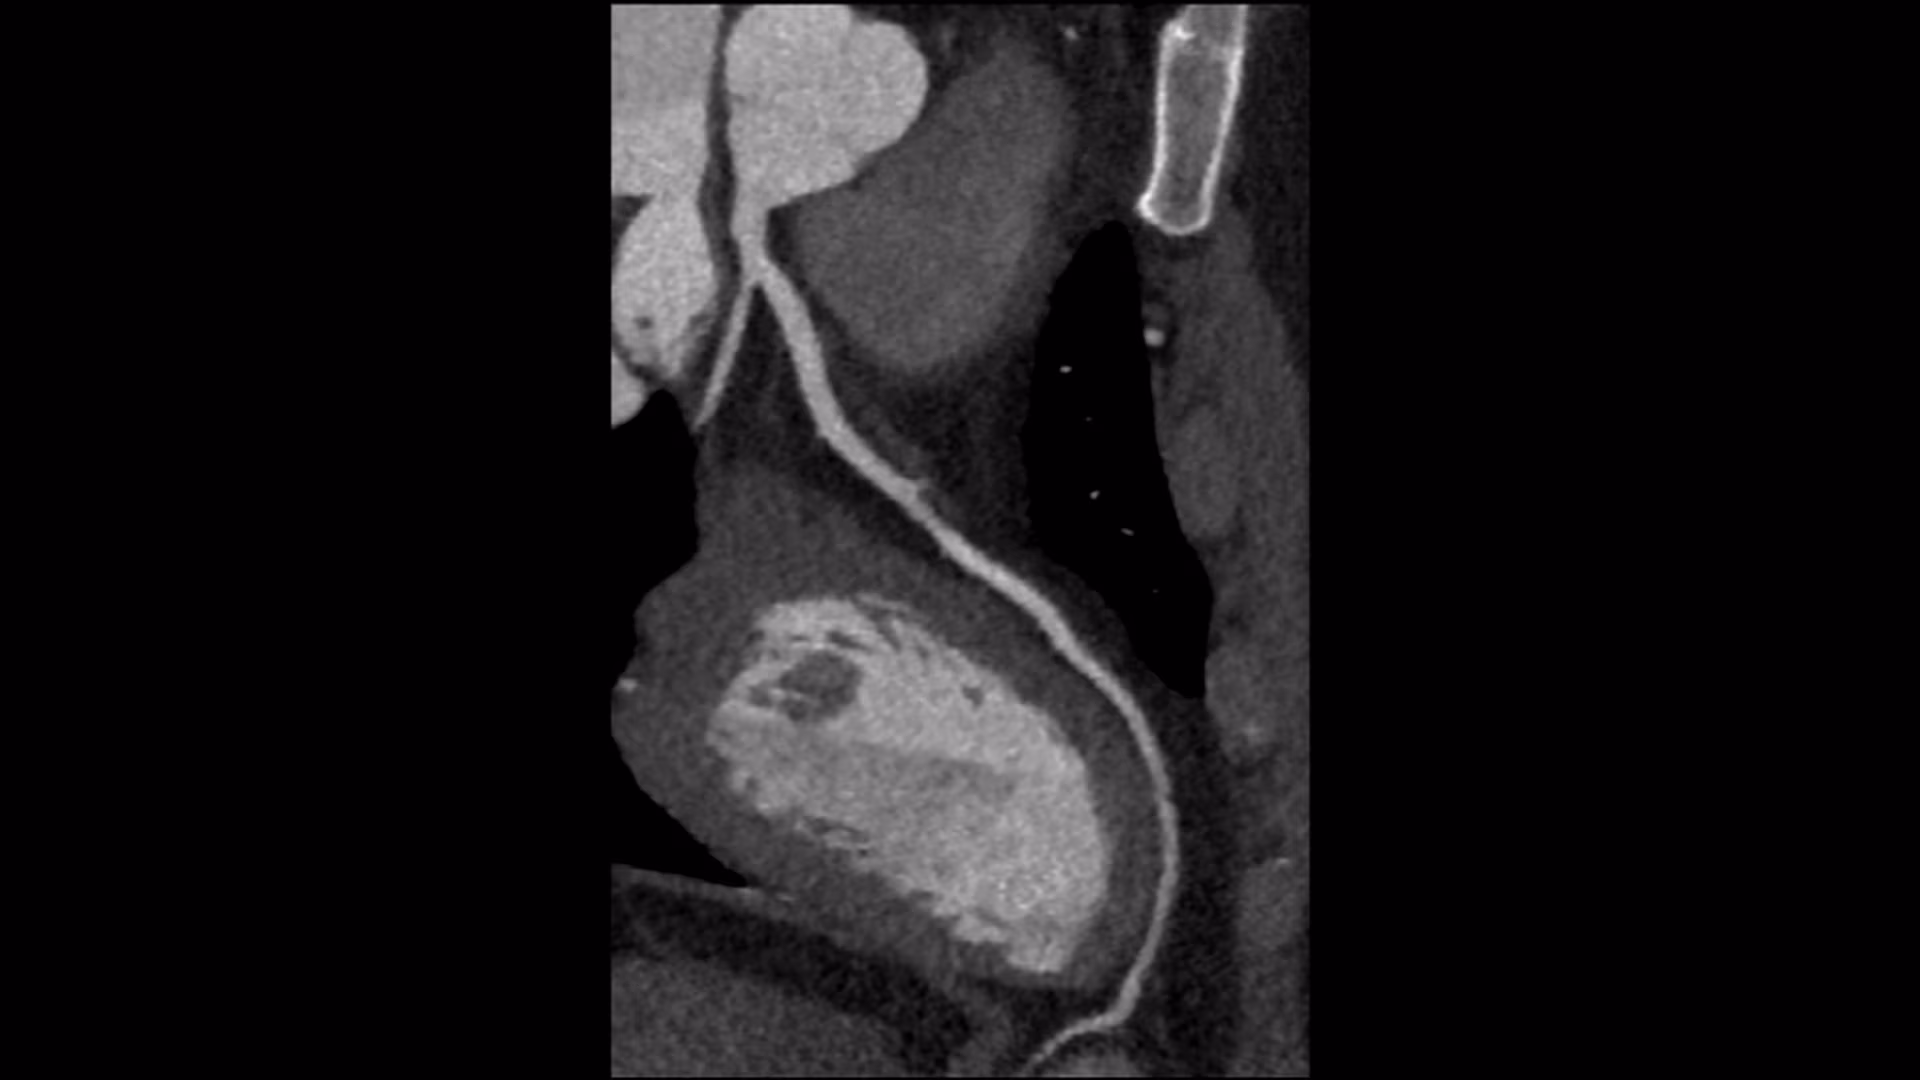

Discover the power of precise heart imaging with our Cardiac CT services, featuring the advanced Revolution Maxima CT. Designed with your comfort and care in mind, this state-of-the-art technology provides fast, accurate insights into your heart health, helping you and your doctor make informed decisions.

Our Cardiac CT uses the Revolution Maxima CT to deliver high-quality images of your heart and blood vessels in just minutes. This non-invasive scan helps detect heart conditions early, offering you peace of mind and a clear path to better health. With its speed and precision, the Revolution Maxima ensures reliable results with minimal discomfort.